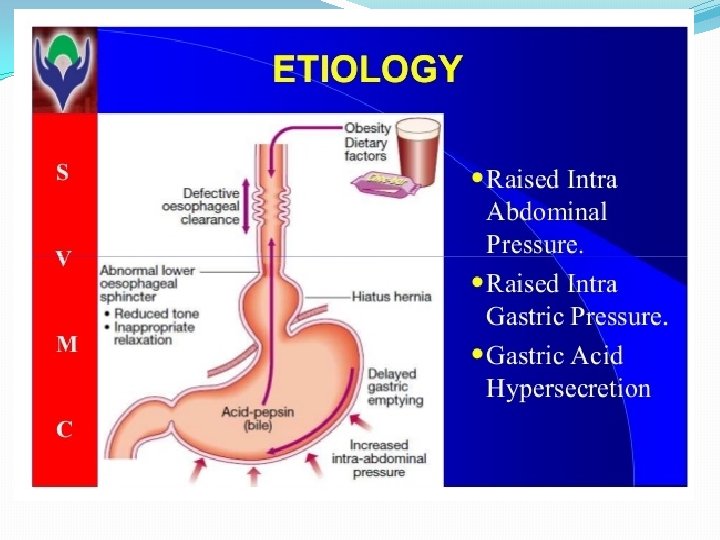

Pathophysiology Antireflux barrier: *lower esophageal sphincter (LES) *the crura of the diaphragm *gastroesophageal junction anatomy

The mechanisms involved in the pathogenesis of GERD are multiple and include: 1. impaired LES resting tone 2. increased number of transient LES relaxations (TLESR) 3. Gastric distention (delayed gastric emptying, large fatty meals) can significantly increase the rate of transient LES relaxations) 4. hiatal hernia (promoting lower oesophageal sphincter dysfunction)

5. Impaired oesophageal acid clearance (this process involves peristalsis as well as the swallowing of salivary bicarbonate) lead to prolonged acid exposure of the mucosa. 6. increase intra-abdominal pressure (straining, obesity, coughing, wheezing).